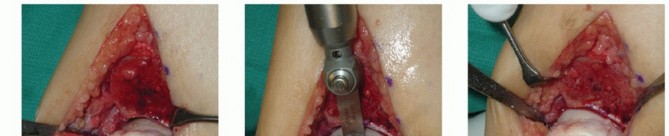

Only once have we had a graft match perfectly on the first attempt. The graft and recipient site will almost always need to be tailored slightly to allow optimal graft fit.

It is unlikely that a perfect clinical and fluoroscopic match will be achieved. Attempt to achieve the best clinical match of the graft's articular surface with the surrounding native cartilage (TECH FIG 4A).

If the clinical match is appropriate, then the fluoroscopic match is not important.

There is a lot of variability in cartilage thickness and talar architecture in the human talus. It is difficult to get four surfaces to congruently match.

Graft fixation

Ideally, the graft will have some interference fit.

We routinely secure the graft with one or two small-diameter solid screws (1.5 or 2.0 mm in diameter). One is typically placed from dorsal to plantar and the other from medial to lateral (if the depth of the graft will allow) (TECH FIG 4B,C).

Place the screws in lag fashion.

Countersink the screw heads below the articular surface (TECH FIG 4D,E).

Using fluoroscopy, confirm that the graft and hardware are in optimal position (TECH FIG 4F-H).

The graft will not look perfect fluoroscopically, but as long as the clinical appearance is acceptable, the outcome has a good chance to be favorable.

The hardware may appear slightly proud fluoroscopically despite being countersunk. The talar dome is not a flat plane, and therefore the screw may seem to be protruding. Moreover, the articular cartilage is rather thick compared to such a low-profile screw head.

- TECH FIG 4 • A-C. Fitting and securing the graft to the native talus. A. After contouring the graft (some minor discoloration from debris while manipulating graft on back table; it is easily washed away). B. Drill hole perpendicular to graft. C. Securing graft with two countersunk screws. (continued)